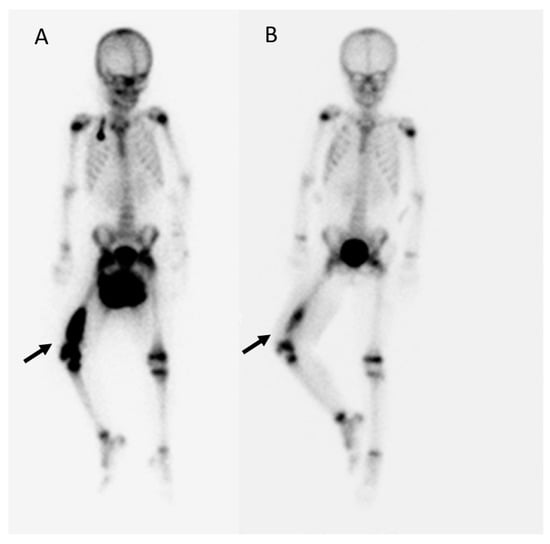

3.4. Everolimus Showed a Promising Effect When Given in Combined Salvage Therapy